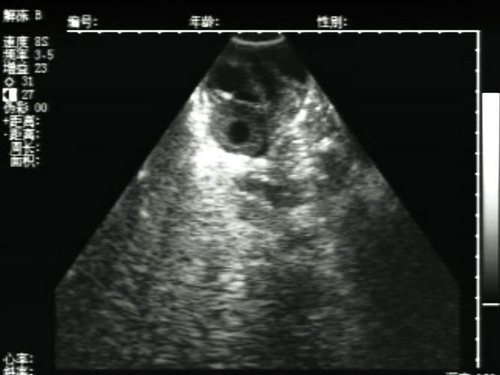

来月经期间能做b超检查吗(图片来源网络)